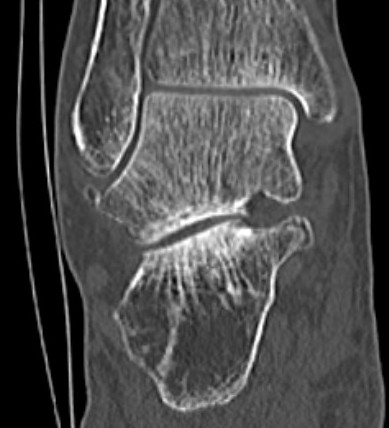

Subluxation of TNJ with advanced STJ OA

TNJ OA with posterior / medial / anterior facet OA of the subtalar joint